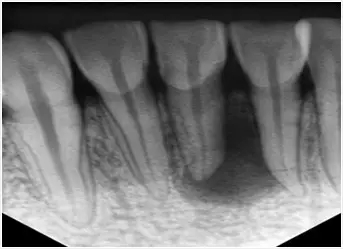

拍片查看牙齒是否需要再次根管治療

1、及時到醫院找醫生複診,拍牙片查看根管治療情況,確定是否存在治療不完善需要重新治療的情況。